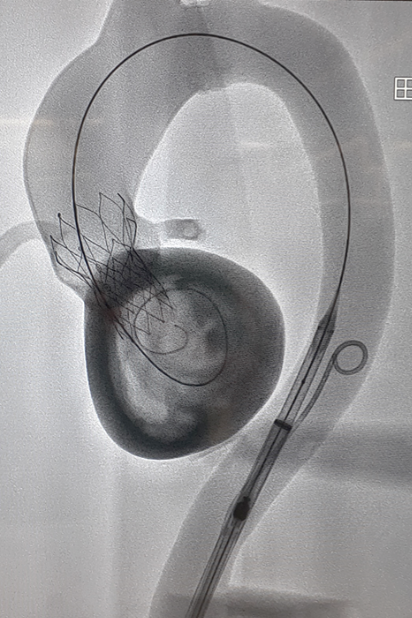

Optimierung der VAD-Implantation durch 3D-Modellierung

Dieses Projekt zielt auf die Entwicklung quantitativer Messungen der Positionierung von VADs (Ventricular Assist Device) anhand von 3D-Modellen von PatientInnen und klinischen Daten ab, um anschließend Korrelationen zwischen der Position und den Therapieergebnissen wie dem Auftreten von Thrombosen, Schlaganfällen und Absaugungen zu ermitteln. Auf der Grundlage dieser Erkenntnisse wird ein standardisiertes Protokoll für qualitativ hochwertige Bildgebung für 3D-gedruckte Modelle entwickelt, das eine verbesserte präoperative Planung und eine minimalinvasive VAD-Implantation ermöglicht. Dieses Projekt wurde durch das externe Forschungsprogramm von Medtronic finanziert.